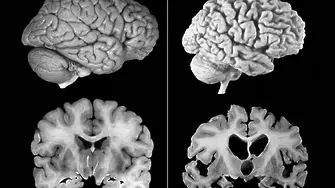

Амилоидните пептиди се превръщат в токсични плаки в мозъка, които увреждат невроните, поясниха учените.